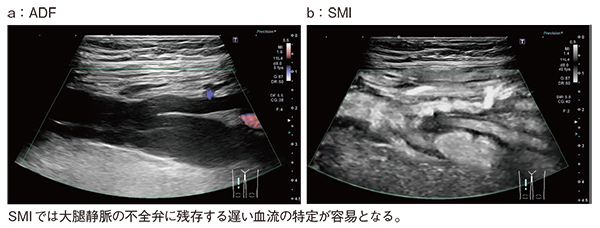

図6は大腿静脈で,ADF(a)でも逆流の有無は視認できるが,SMI(b)では逆流に加え,不全弁周囲に残存する遅い血流の特定も容易である。

図6 SMIによる不全弁周囲の低流速部位の特定